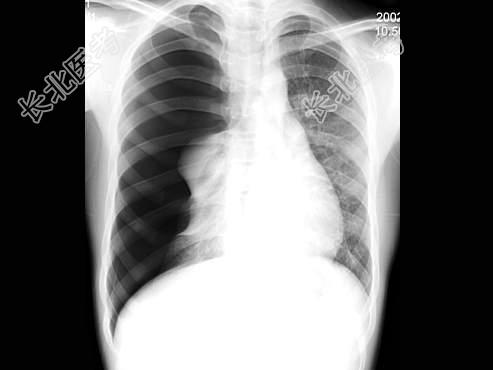

- 单项选择题男,16岁, 突感呼吸困难,大汗淋漓, 胸片检查如图,最可能的诊断是 ( )

A、右侧肺气肿

B、右侧肺部肿块

C、右侧气胸

D、右侧肺大泡

E、右侧肺挫伤